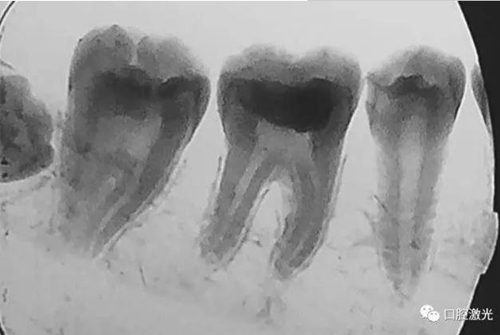

活髓理療治療結(jié)果令人滿意,沒(méi)有出血,也沒(méi)有出現(xiàn)碳化?;颊邲](méi)有感受到不適并表示滿意。為了跟蹤激光輔助活髓切除術(shù)的治療效果,手術(shù)完成即刻和5周后分別拍攝了X光圖像。5周后的牙髓活性溫度測(cè)試也顯示陽(yáng)性。

治療后5周